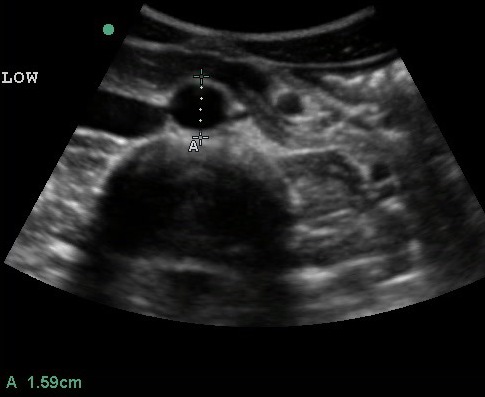

- Figure 7. Transverse view of a 4.1 cm AAA

Video 4. Transverse view of large AAA